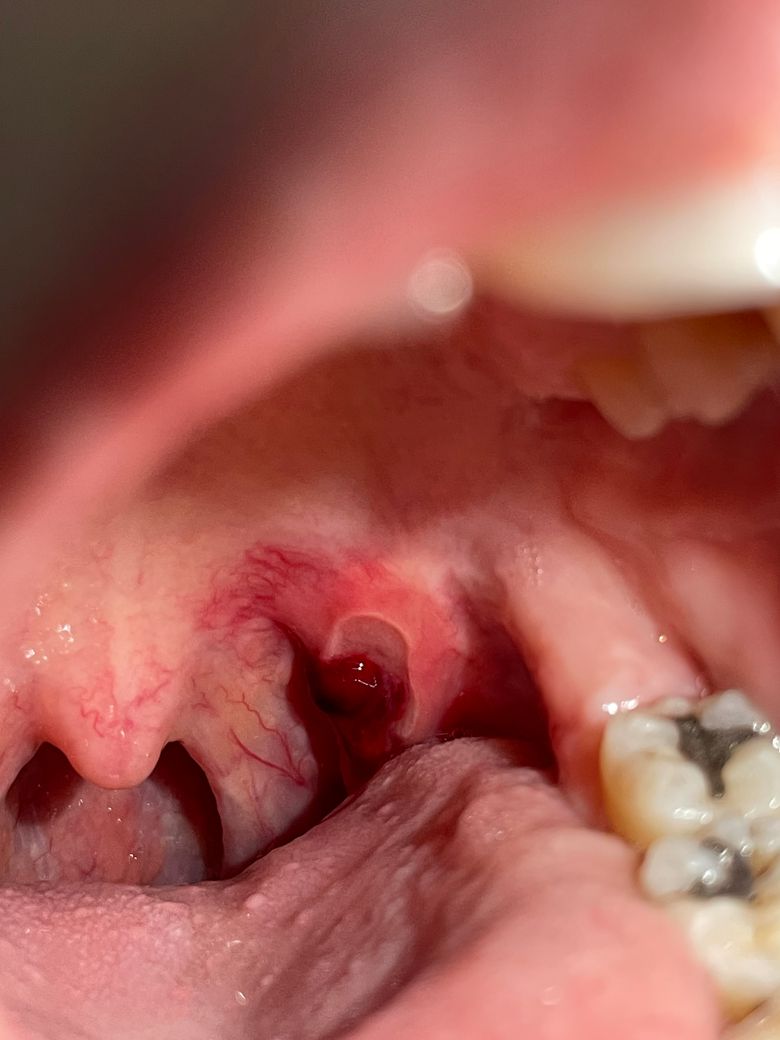

구내염이 심해져서 피고름이 생겼어요

목구멍으로 넘어가는 쪽에 하얗게 헐어있던게 오늘은 피고름이 생겨서 겁이 나네요

• 1번 째 사진